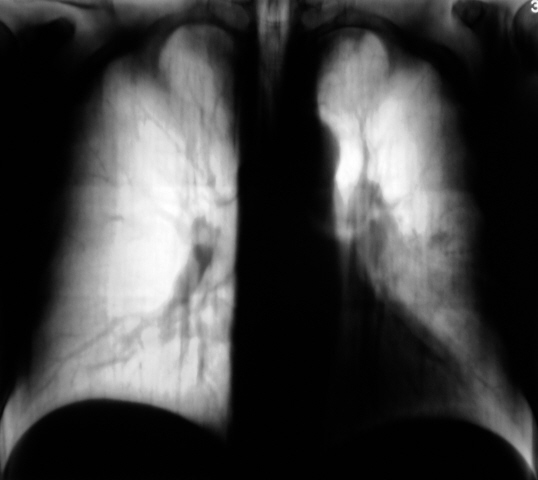

Направили пациента на консультацию к онкологам. Коллеги! Ваше мнение.

Переферическое образование(вероятнее Cr), какой некрасивый левый корень-лимфоаденопатия.

А вот с татьяной луневой поспорю: самое, что ни на есть центральное, а в корне, кроме аденопатии, еще и обтурация.

ИМХО здесь обтурация соустья Br 4 и Br5. Массивные метастазы в бронхо-пульмональные л/узлы. Очень массивные. А на картинках полученных в результате цифровой обработки рентгенограмм они «слиняли», потому и перисциссурит. Но и периферическое образование слева на томограммах тоже выявляется.